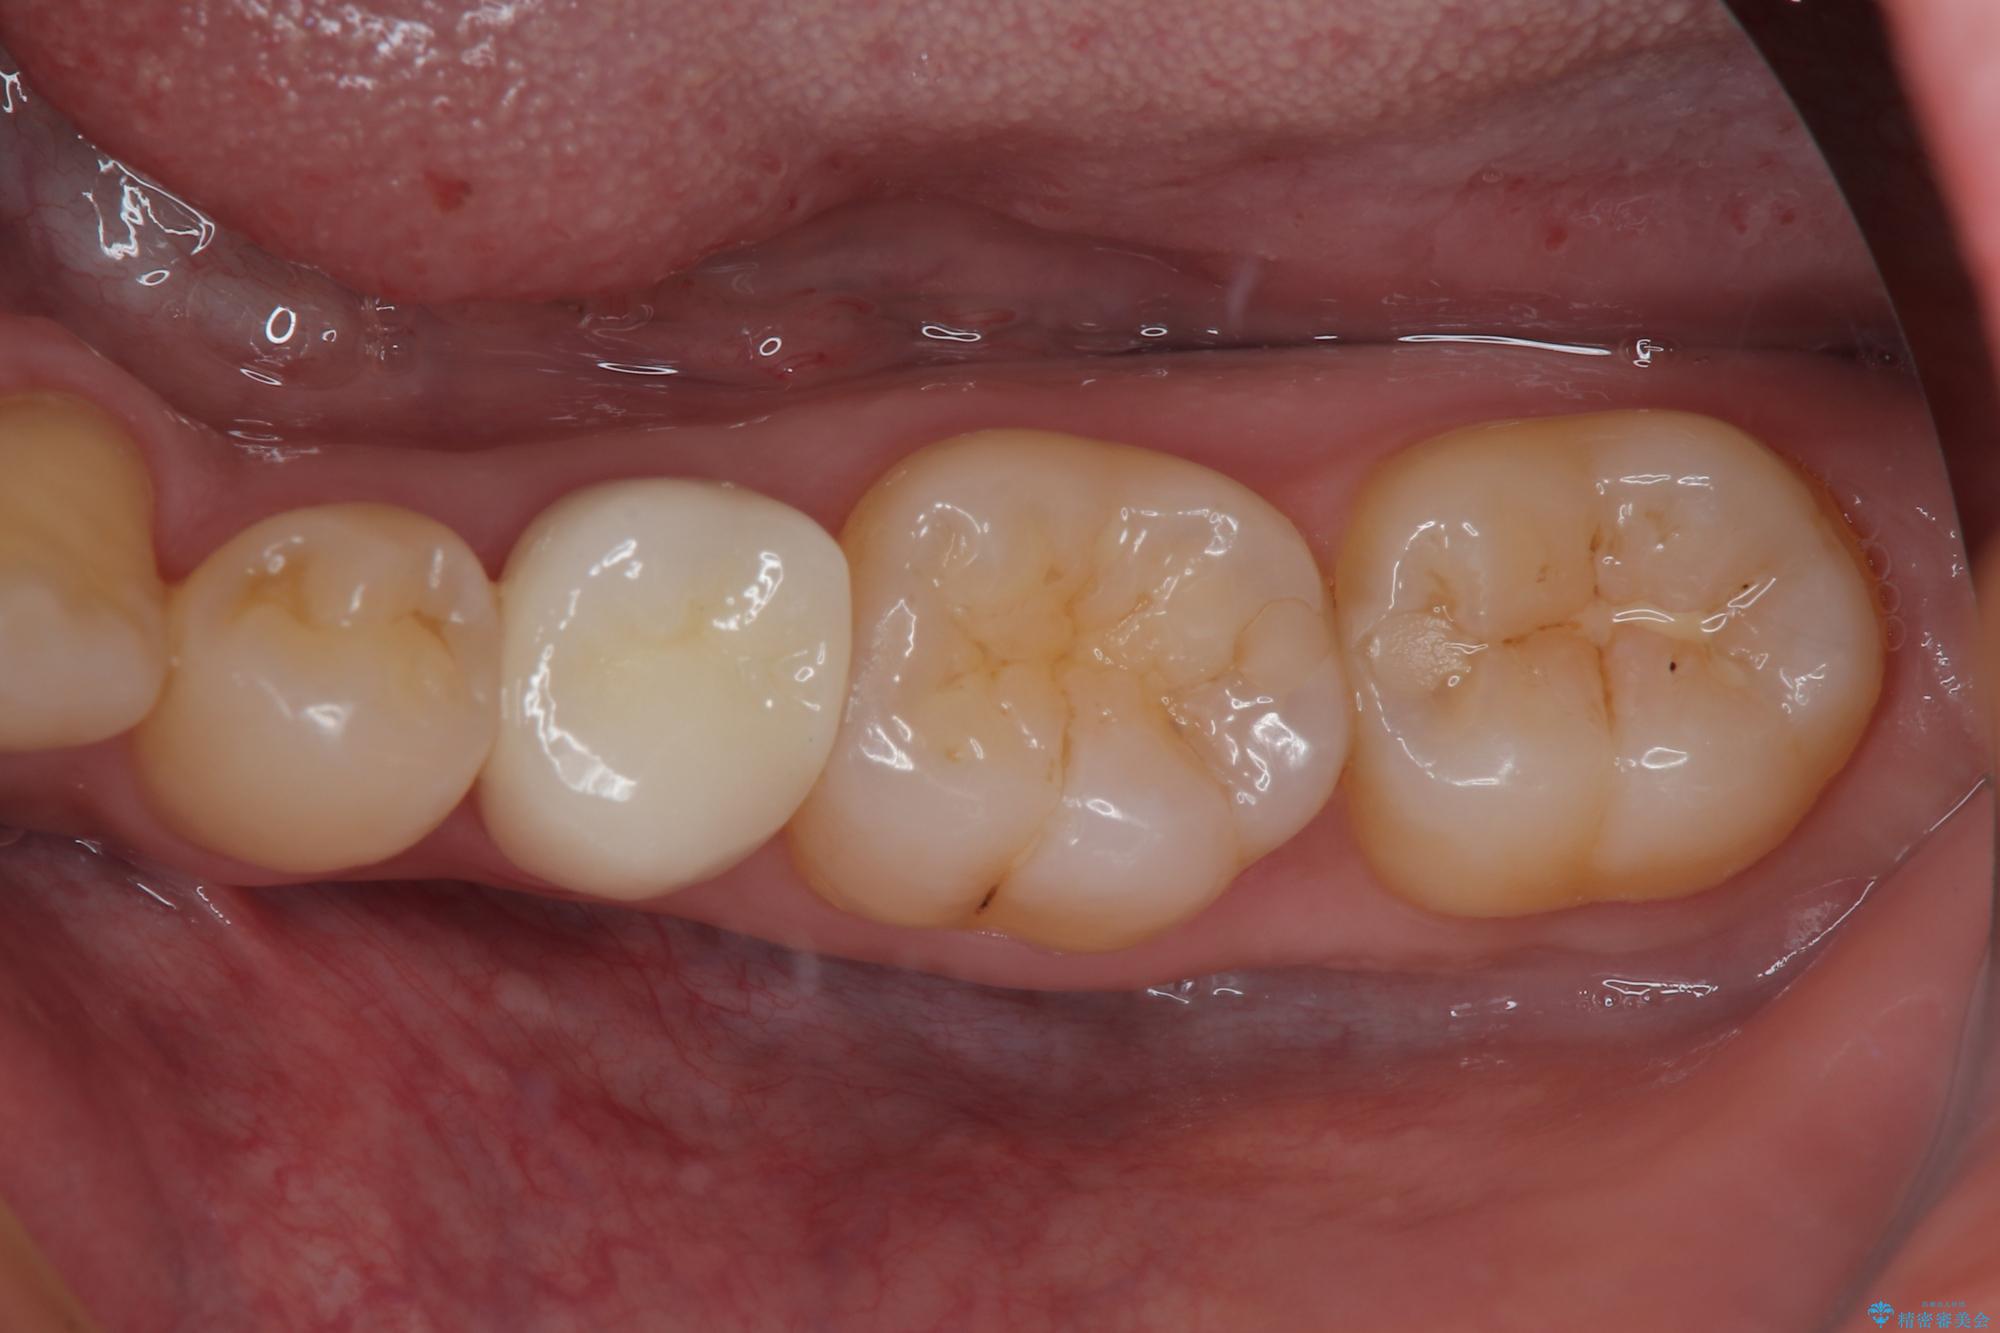

左下にフロスを通すと引っかかる オールセラミッククラウン

- 左下の奥歯のところがフロスが引っかかったり、ちぎれたりするとのことで来院された患者様です。検査の結果、神経は正常な反応を示し、フロスは引っかかる状態でしたので、虫歯治療も併せて行うためにオールセラミッククラウンによる補綴治療を行っていくことにしました。

拡大鏡視野下でプラスチックの詰め物、虫歯を除去しオールセラミッククラウンに適した形に整えました。

フロスがちぎれることもなくなり、被せものが入っていることを忘れていたと大変喜んでいただきました。適合の良い被せものは二次的な虫歯の再発リスクを低減してくれます。

今後の予定は患者様のタイミングで歯茎から少し見えている親知らず抜歯を行っていく予定です。